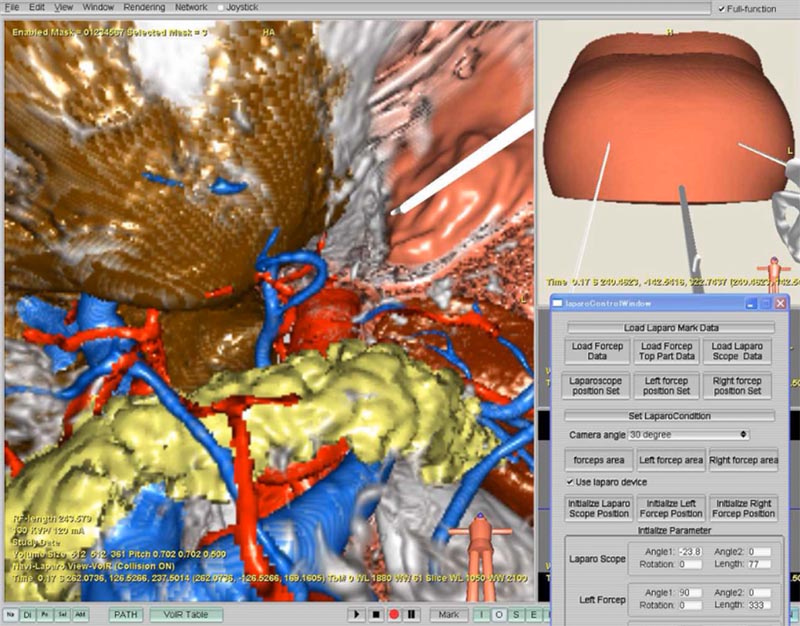

外科手術支援システムの開発も、森研究室の重要な研究テーマです。森研究室では、名大病院、愛知県がんセンターなどと協力しながら研究を進めています。手術ナビゲーションとは、手術中にカーナビゲーションのように、医師をナビゲーションするシステムのことです。また、手術前に、手術に役立つ3次元画像を生成することも、広義には手術ナビゲーションと呼ばれています。

腹腔鏡手術ナビゲーションでは、内視鏡、鉗子(手術に用いる棒状のはさみです)に位置センサを装着します。位置センサから得られる情報を基に、内視鏡画像に対応する仮想化内視鏡画像を生成し、現在どのあたりを見ているのかを分かりやすく表示します。また、鉗子位置も仮想化内視鏡画像上に表示することができます。これによって、鉗子位置は切除などの対象部位かどうかを容易に判断することができるようになります。

図5 腹腔鏡手術ナビゲーションの例